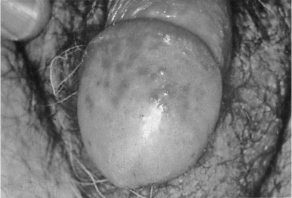

1.4.2.7.3三、临床表现